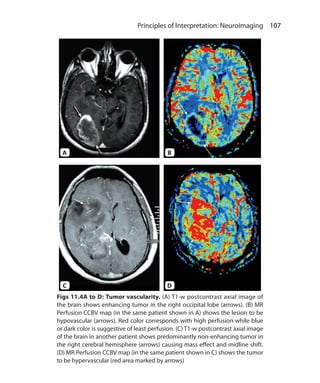

• 8.

Commonly Used ShortForms ADC Analog to Digital Converter CEMRA Contrast Enhanced MR Angiography FOV Field of View FT Fourier Transformation GMR Gradient Motion Rephasing/Nulling GRE Gradient Echo IR Inversion Recovery LM Longitudinal Magnetization MTC Magnetization Transfer Contrast NEX Number of Excitation (Averages of Acquisition) NMV Net Magnetization Vector PD Proton Density RF Radiofrequency SAR Specific Absorption Rate SE Spin Echo SNR Signal to Noise Ratio TE Time to Echo TI Time to Invert (Inversion Time) TM Transverse Magnetization TR Time to Repeat VENC Velocity Encoding

• 9.

SEQUENCES SIEMENS* GE* PHILIPS* 1. Spin Echo Sequences Conventional SE (90–180° RF pulses) SE SE SE Double SE (90° followed by two 180° RF pulses) PD/T2 PD/T2 PD/T2 Multi-SE (90° followed by multiple 180° RF pulses) Turbo SE Fast SE Turbo SE Multi-SE with flip-back 90°pulse RESTORE FRFSE DRIVE Single-shot Multi-SE (Multi-SE with half K-Space filling) HASTE Single Shot FSE Ultrafast SE Radial K-Space filling BLADE PROPELLER MultiVane 2. Gradient Echo Sequences A. Incoherent spoiled TM FLASH SPGR T1-FFE 3D versions 3D FLASH VIBE LAVA FAME THRIVE B. Coherent/Rephased TM 1. Post-excitation refocused (FID sampled) FISP GRASS FFE 2. Pre-excitation refocused (Spin echo sampled) PSIF SSFP T2-FFE 3. Fully refocused (both FID & spin echo sampled) True FISP FIESTA Balanced FFE 3. Inversion Recovery Sequences Short TI (80–150 ms), e.g. STIR Medium TI (300–1200 ms), e.g. MPRAGE Long TI (1500–2500 ms), e.g. FLAIR 4. Hybrid Combination of SE and GRE TGSE GRASE GRASE 5. EPI Single shot Multishot-segmented *Vendor nomenclatures for sequences are taken from References—1. Nitz WR. MR Imaging: Acronyms and clinical applications. Eur Radiol. 1999;9:979-97. and 2. Brown MA, Semelka RC. MR Imaging Abbreviations, Definitions, and Descriptions: A Review. Radiol. 1999; 213:647-62. Trade Names of Sequences

• 11.

Contents Section 1 Chapter 1. Basic Principles 1 Longitudinal Magnetization 2 Transverse Magnetization 3 MR Signal 4 Localization of the Signal 5 Chapter 2.  T1, T2 Relaxations and Image Weighting 8 Longitudinal Relaxation  8 Transverse Relaxation  9 T1  10 T2  11 T2* (T2 star)  11 TR and TE  12 TI  13 T1 Weighted Image  13 T2 Weighted Image  14 Proton Density (PD) Image  16 Chapter 3.  K-Space and Scanning Parameters 17 K-Space 17 Parameters of Scanning 18 Image Quality Determinants 20 Chapter 4.  Magnetic Resonance Instrumentation 22 Magnetism 22 Magnetic Field Strength 23 Magnets 24 Gradients 29 Radiofrequency Coils 30 Computers and Accessories 32 Chapter 5.  Sequences I: Basic Principles and Classification 33 Classification 34 Spin Echo (SE) Pulse Sequence 34 Gradient Echo (GRE) Sequence 37

• 12.

xviii  MRI MadeEasy (for Beginners) Inversion Recovery (IR) Sequence 40 Echo Planar Imaging (EPI) 44 Chapter 6.  Sequences II: Accessory Techniques 47 Fat Suppression 47 Parallel Imaging 52 Respiratory Compensation Techniques 53 Gradient Moment Rephasing (GMR) 53 Magnetization Transfer 55 Keyhole Imaging 56 Saturation Band 56 Chapter 7.  Sequences III: When to Use What Sequences 58 T1- Weighted Sequences 58 T2-Weighted Sequences 61 T2* Weighted Sequences 70 Cartilage Sensitive Sequences 70 Chapter 8.  Magnetic Resonance Imaging Artifacts 73 Ghosts/Motion Artifacts 73 Aliasing/ Wraparound 75 Chemical Shift Related Artifacts 76 Truncation Artifact 78 Magnetic Susceptibility Artifact 78 Straight Lines and Zipper Artifacts 80 Shading Artifacts 81 Cross Excitation and Cross Talk 82 Parallel Imaging Artifact 84 Chapter 9.  Magnetic Resonance Safety 85 MR Bioeffects 85 Safety Related Issues 86 Chapter 10.  Magnetic Resonance Contrast Media 91 Classification of MR Contrast Media 91 Mechanism of MR Contrast Enhancement 92 Gadolinium 93 Nephrogenic Systemic Fibrosis (NSF) 96 Other MR Contrast Agents 97 Oral Contrast Agents 98 Role of Contrast in MRI 98